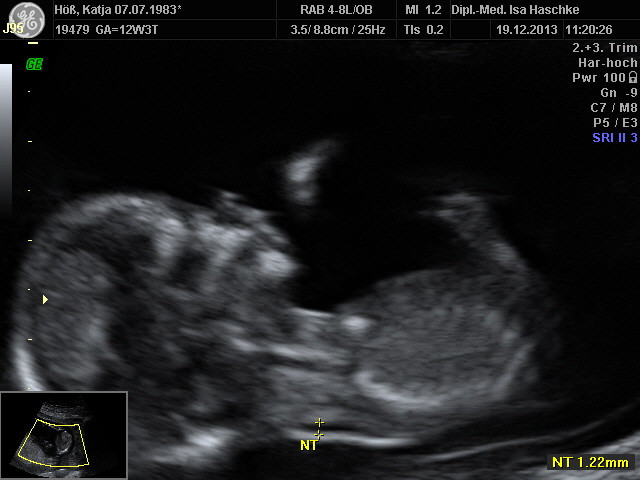

Schwangerschaftswoche 13

Nach unserer Zustimmung und Einverstandnis konnte nun die Nackenfaltenmessung des ungeborenen gemacht werden, am 19.12.2013 wurde diese durchgeführt. Der Befund ist positiv ausgefallen, zu 0,0083 % konnte eine Fehlbildung ausgeschlossen werden, worüber wir sehr glücklich sind.